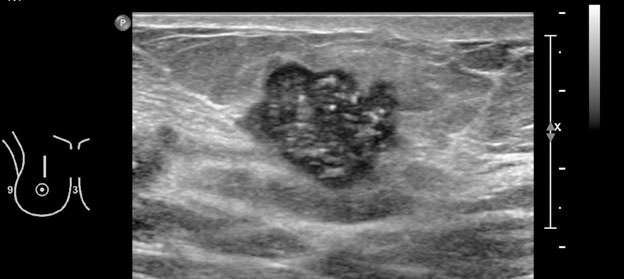

3. Irregular: the shape of the mass is neither round nor oval (Figure 3).

Mammography: Masses Figure 3

Figure 3: A) Mammography of the left breast with MLO view demonstrates irregular, spiculated mass in the left breast at 12 o'clock (big white circle). Additional calcifications in the left breast at 8 o'clock at anterior depth located 2 centimeters from the nipple, three additional groups of calcifications in the central and lower inner left breast are also suspicious (small white circles). B) Ultrasound of the left breast represents an irregular, spiculated hypoechoic mass, BI-RADS Category: 4C suspicious finding. Ultrasound guided biopsy was recommended and confirmed invasive ductal carcinoma, grade 2.